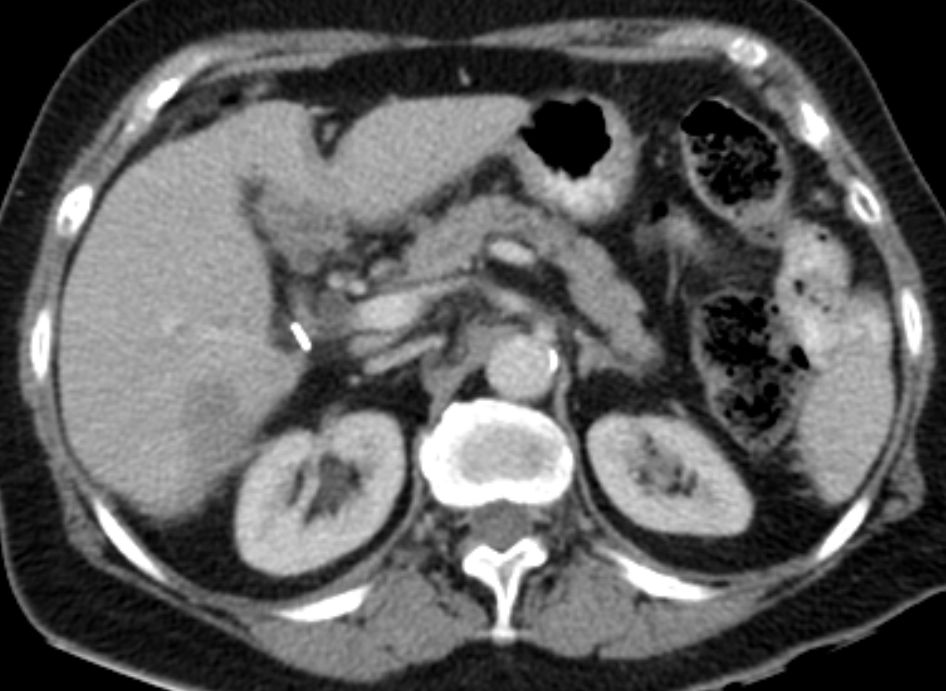

76-jährige Frau, die vor 13 Jahren ein Ovarial-Karzinom pT3b pNo Mo Lo Vo G2 hatte. Radikale OP, 6x Taxol - Carboplatin. Jetzt Lebermetastasen, RF linker Adnexbereich.